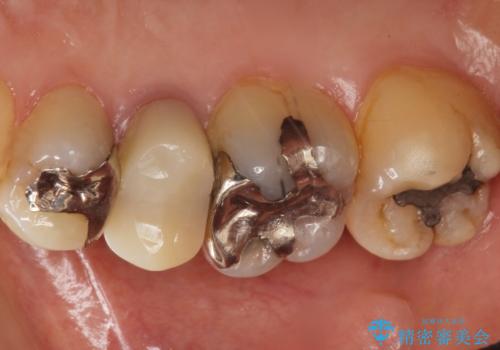

- 歯が欠けてしまったことを主訴に来院された患者様です。

欠けている奥歯(左上5)は失活歯で、保険内の銀の詰め物(メタルアンレー)で治療されていました。

金属の詰め物と土台を除去し、ファイバーコア(金属を使わない強くてしなやかな土台)を植立したのちセラミッククラウンによる補綴治療を行いました。

精査したところ、右上の奥歯(右上5)に根尖病変を認めたため、こちらは根管治療後にセラミッククラウンによる補綴を行いました。